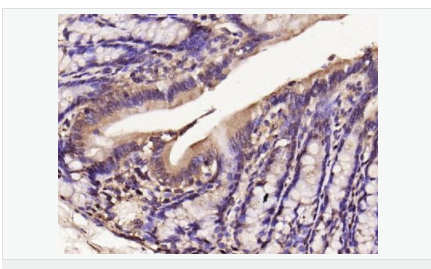

| 產(chǎn)品介紹 | Nitric oxide (NO) is an inorganic, gaseous free radical that carries a variety of messages between cells. Vasorelaxation, neurotransmission and cytotoxicity can all be potentiated through cellular response to NO. NO production is mediated by members of the nitric oxide synthase (NOS) family. NOS catalyzes the oxidization of L-arginine to produce L-citrulline and NO. Two constitutive isoforms, brain or neuronal NOS (b or nNOS, type I) & endothelial cell NOS (eNOS, type III), and one inducible isoform (iNOS, type II), have been cloned. All NOS isoforms contain calmodulin, nicotinamide adenine dinucleotide phosphate (NADPH), flavin adenine dinucleotide (FAD), and flavin mononucleotide (FMN) binding domains. Nitric oxide synthase is expressed in liver, macrophages, hepatocytes, synoviocytes, stimulated glial cells and smooth muscle cells. Cytokines such as interferon-gamma (IFN), tumor necrosis factor (TNF), interleukin-1 and -2, and lipopolysaccarides (LPS) cause an increase in iNOS mRNA, protein, and activity levels. Protein kinase C-stimulating agents exhibit the same effect on iNOS activity. After cytokine induction, iNOS exhibits a delayed activity response which is then followed by a significant increase in NO production over a long period of time. Human iNOS is regulated by calcium/calmodulin (in contrast with mouse NOS2). Function: Produces nitric oxide (NO) which is a messenger molecule with diverse functions throughout the body. In macrophages, NO mediates tumoricidal and bactericidal actions. Also has nitrosylase activity and mediates cysteine S-nitrosylation of cytoplasmic target proteins such COX2. Subunit: Homodimer. Binds SLC9A3R1. Tissue Specificity: Expressed in the liver, retina, bone cells and airway epithelial cells of the lung. Not expressed in the platelets. Similarity: Belongs to the NOS family. Contains 1 FAD-binding FR-type domain. Contains 1 flavodoxin-like domain. SWISS: P35228 Gene ID: 4843 Database links: Entrez Gene: 4843 Human Entrez Gene: 18126 Mouse Omim: 163730 Human SwissProt: P35228 Human SwissProt: P29477 Mouse Unigene: 709191 Human Unigene: 2893 Mouse Unigene: 10400 Rat Important Note: This product as supplied is intended for research use only, not for use in human, therapeutic or diagnostic applications. 合成與降解(Synthesis and Degradation) 催化生物體內(nèi)一氧化氮(NO)生成的酶。分神經(jīng)型一氧化氮合成的酶(nNOS or NOS-1)、誘導(dǎo)型一氧化氮合成的酶(iNOS or NOS-2)、內(nèi)皮型一氧化氮合成的酶(eNOS or NOS-3)。 |